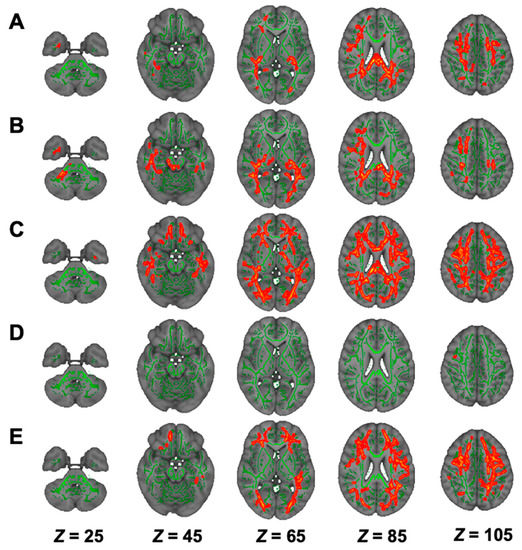

| Modality | Contrast | Cluster Size | Anatomical Region | Peak t-Value | Peak MNI Coordinates (X, Y, Z) |

|---|---|---|---|---|---|

| DTI | |||||

| FA | HC > NSTLC | 48,825 | Bilateral ATR, corticospinal tract, CCG, forceps minor and major, IFOF, ILF, SLF, SLF temporal part, medial lemniscus, CP, ALIC, PLIC, retrolenticular part of IC, ACR, SCR, PCR, PTR, SS, external capsule, fornix stria terminalis, SFOF, tapetum; left UF, corticospinal tract, ICP, UF; right SCP; MCP, pontine crossing tract, genu, body and splenium of CC, fornix | 6.74 | (74, 69, 105) |

| AD | HC < NSTLC | 10,699 | Bilateral ATR, corticospinal tract, IFOF, SLF, ALIC, PLIC, retrolenticular part of IC, ACR, SCR, PCR, PTR, external capsule, fornix stria terminalis, SFOF; left ILF, SS, tapetum; forceps minor, UF, genu, body and splenium of CC, fornix | 5.85 | (50, 125, 100) |

| RD | HC < NSTLC | 49,556 | Bilateral ATR, corticospinal tract, CCG, IFOF, ILF, SLF, UF, SLF temporal part, CP, ALIC, PLIC, retrolenticular part of IC, ACR, SCR, PCR, PTR, SS, external capsule, fornix stria terminalis, SFOF, tapetum; forceps minor and major, genu, body and splenium of CC, fornix | 7.43 | (140, 117, 50) |

| MD | HC < NSTLC | 43,676 | Bilateral ATR, corticospinal tract, CCG, IFOF, ILF, SLF, UF, SLF temporal part, ALIC, PLIC, retrolenticular part of IC, ACR, SCR, PCR, PTR, SS, external capsule, fornix stria terminalis, SFOF, tapetum; left CHp; forceps minor and major, genu, body and splenium of CC, fornix | 7.10 | (53, 104, 105) |

| DKI | |||||

| AK | HC > NSTLC | 15,653 | Bilateral corticospinal tract, IFOF, ILF, SLF, PLIC, retrolenticular part of IC, ACR, SCR, PCR, PTR, external capsule, fornix stria terminalis, tapetum; right ATR, cingulum hippocampus, UF, SS, CCG, CHp; forceps minor and major, body and splenium of CC | 6.03 | (53, 65, 61) |

| HC > LTLC | 16,138 | Bilateral corticospinal tract, CHp, IFOF, ILF, SLF, SLF temporal part, corticospinal tract, medial lemniscus, SCP, CP, PLIC, retrolenticular part of IC, SCR, PCR, PTR, SS, fornix stria terminalis, tapetum; left ATR, UF, ALIC, ACR, external capsule, SFOF; forceps major, MCP, pontine crossing tract, body and splenium of CC | 6.19 | (55, 92, 82) | |

| RK | HC > NSTLC | 45,239 | Bilateral ATR, corticospinal tract, CCG, IFOF, ILF, SLF, UF, SLF temporal part, ALIC, retrolenticular part of IC, ACR, SCR, PCR, PTR, SS, external capsule, fornix stria terminalis, SFOF; right UF, tapetum; forceps minor and major, genu, body and splenium of CC | 6.11 | (98, 172, 110) |

| HC > LTLC | 69 | forceps minor | 4.89 | (79, 177, 101) | |

| MK | HC > NSTLC | 28,546 | Bilateral ATR, IFOF, ILF, SLF, ALIC, ACR, SCR, PCR, PTR, SS, external capsule, SFOF; left corticospinal tract, UF, retrolenticular part of IC; forceps minor and major, genu, body and splenium of CC | 6.82 | (97, 141, 131) |

| NODDI | |||||

| ICVF | HC > NSTLC | 67,959 | Bilateral ATR, corticospinal tract, CCG, IFOF, ILF, SLF, UF, SLF temporal part, CP, ALIC, PLIC, retrolenticular part of IC, ACR, SCR, PCR, PTR, SS, external capsule, CHp, fornix stria terminalis, SFOF, tapetum; left UF; right CHp; forceps minor and major, genu, body and splenium of CC | 8.15 | (106, 82, 84) |

| HC > LTLC | 38,021 | Bilateral ATR, corticospinal tract, CCG, IFOF, ILF, SLF, UF, SLF temporal part, ALIC, PLIC, retrolenticular part of IC, ACR, SCR, PCR, PTR, SS, external capsule, CHp, fornix stria terminalis, SFOF; left tapetum; right CHp, CP; forceps minor and major, genu, body and splenium of CC | 6.22 | (113, 63, 103) | |

| ISO | HC > LTLC | 3978 | right ATR, Inferior fronto-occipital fasciculus, ILF, UF, retrolenticular part of IC, ACR, SCR, PTR, SS; forceps minor and major | 5.88 | (48, 116, 49) |

| NSTLC > LTLC | 8312 | Bilateral corticospinal tract, IFOF, ILF, SLF, UF, SCP, CP, retrolenticular part of IC, PTR, SS; right ATR, CHp, SLF temporal part, ALIC, PLIC, external capsule, fornix stria terminalis; forceps minor and major, MCP, pontine crossing tract | 7.52 | (129, 83, 68) | |